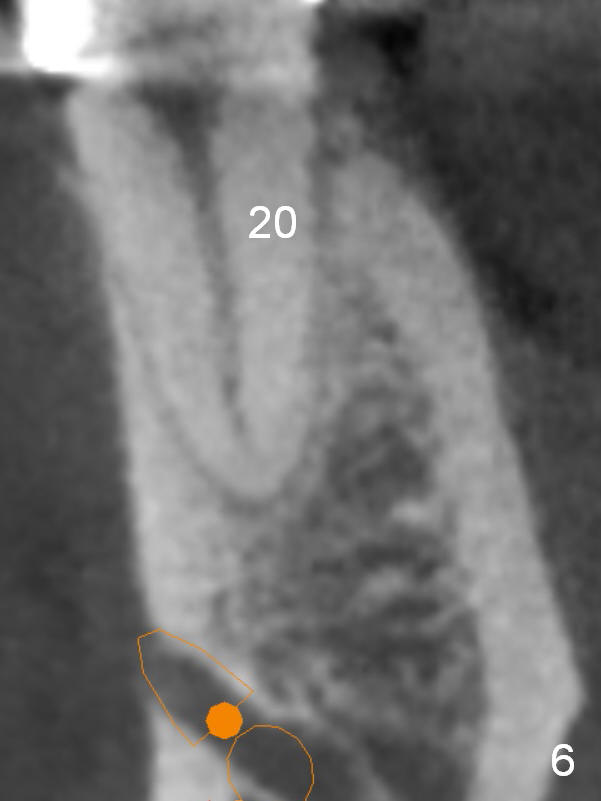

A 35-year-old lady (YL) has periodic nocturnal pain of the lower left quadrant. There is open buccal margin at the abutment of #18 (Fig.1 (from panoramus)). When the pontic and the retainer are removed (Fig.2), there is a large buccal subgingival carious lesion at the tooth #18. The latter has 2 roots, although close to each other. If the extraction turns out to be difficult, section the tooth (Fig.3 red line (no antibiotic)). To avoid contacting the tooth #17, place an implant at the mesial socket of #18 (Fig.5,7). Although it appears that the tooth #20 has no periapical radiolucency (Fig.6,7), the crown will be removed for diagnosis. A 3-unit provisional will be fabricated after an implant is placed at #19 (Fig.7,8) in the same appointment.